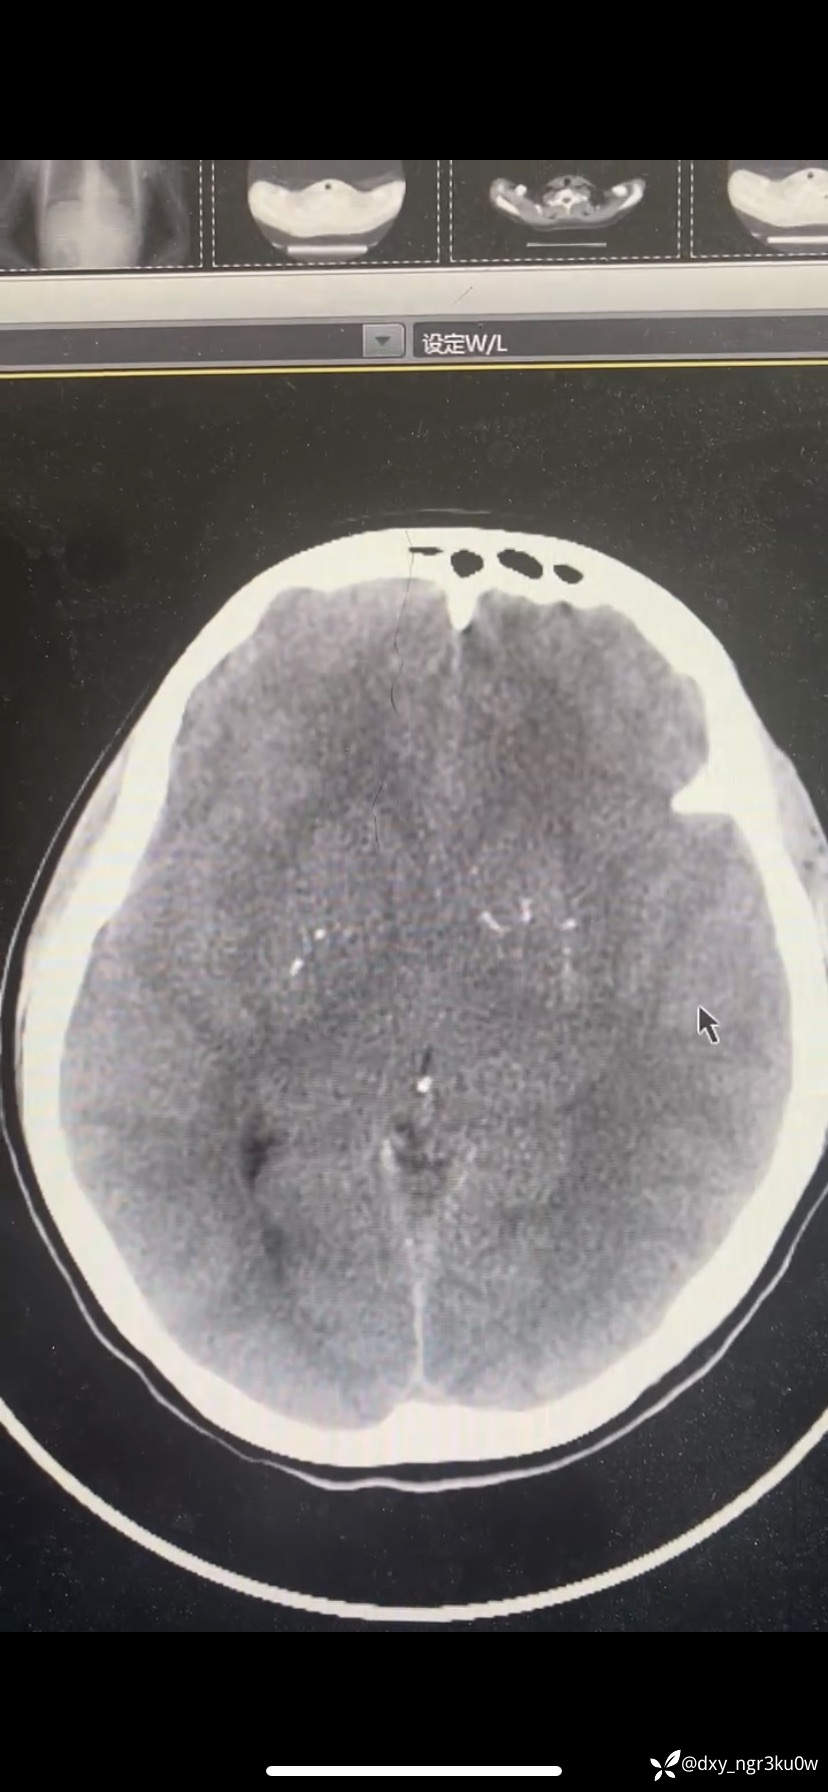

入院血气分析:ph:7.001,PCO2 10.7,PO2 136.6,Na124,K5.18,HCO3- 2.6,Glu>30,Lac1.7。颅脑CT如下